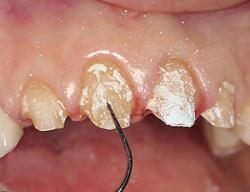

1. For restorations, Astingedent™ X hemostatic and Ultrapak cord are ideal for controlling blood and sulcular fluids and can also protect tissue from burs. Use a firm air/water spray to remove excess hemostatic solution.

1. Packing Ultrapak cord quickly displaces tissues and improves access for indirect veneer luting.

FOR IMPRESSION TAKING

An astringent is a substance that eliminates permeability of epithelium to tissue fluid flow. The result is a dry field, an important tissue management solution. An ideal impression for successful crowns, veneers, and bridges must accurately capture the preparation margins. This can be ensured only through reliable hemostasis and gingival displacement.